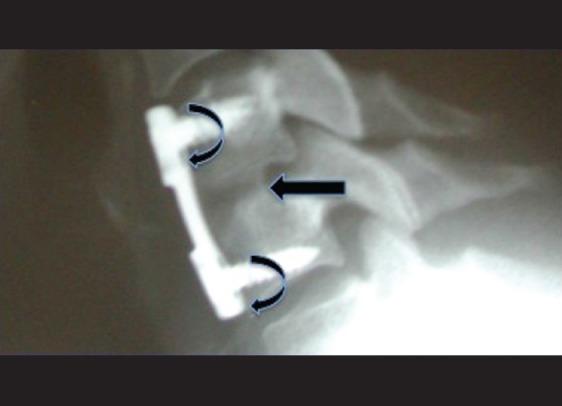

髂嵴自体骨移植与颈椎前路手术的替代植入物:利弊与成本

Iliac crest autograft versus alternative constructs for anterior cervical spine surgery: Pros, cons, and costs.

Grafting choices available for performing anterior cervical diskectomy/fusion (ACDF) procedures have become a major concern for spinal surgeons, and their institutions. The "gold standard", iliac crest autograft, may still be the best and least expensive grafting option; it deserves to be reassessed along with the pros, cons, and costs for alternative grafts/spacers.

Although single or multilevel ACDF have utilized iliac crest autograft for decades, the implant industry now offers multiple alternative grafting and spacer devices; (allografts, cages, polyether-etherketone (PEEK) amongst others). While most studies have focused on fusion rates and clinical outcomes following ACDF, few have analyzed the "value-added" of these various constructs (e.g. safety/efficacy, risks/complications, costs).

The majority of studies document 95%-100% fusion rates when iliac crest autograft is utilized to perform single level ACDF (X-ray or CT confirmed at 6-12 postoperative months). Although many allograft studies similarly quote 90%-100% fusion rates (X-ray alone confirmed at 6-12 postoperative months), a recent "post hoc analysis of data from a prospective multicenter trial" (Riew KD et. al., CSRS Abstract Dec. 2011; unpublished) revealed a much higher delayed fusion rate using allografts at one year 55.7%, 2 years 87%, and four years 92%.

Iliac crest autograft utilized for single or multilevel ACDF is associated with the highest fusion, lowest complication rates, and significantly lower costs compared with allograft, cages, PEEK, or other grafts. As spinal surgeons and institutions become more cost conscious, we will have to account for the "value added" of these increasingly expensive graft constructs.

对于脊柱外科医生及其所在机构而言,可用于颈椎前路椎间盘切除/融合术(ACDF)的移植选择已成为一个主要关注点。“金标准”——自体髂骨移植,可能仍是最佳且成本最低的移植选择;值得对其以及替代移植材料/椎间融合器的利弊和成本进行重新评估。

尽管单节段或多节段ACDF使用自体髂骨移植已有数十年,但植入物行业如今提供了多种替代移植材料和椎间融合器装置(如异体移植物、椎间融合器、聚醚醚酮(PEEK)等)。虽然大多数研究聚焦于ACDF后的融合率和临床结果,但很少有研究分析这些不同结构的“附加值”(如安全性/有效性、风险/并发症、成本)。

大多数研究表明,使用自体髂骨移植进行单节段ACDF时(术后6 - 12个月经X线或CT证实),融合率为95% - 100%。尽管许多异体移植物研究同样报出90% - 100%的融合率(仅术后6 - 12个月经X线证实),但最近一项“对一项前瞻性多中心试验数据的事后分析”(Riew KD等人,CSRS摘要,2011年12月;未发表)显示,使用异体移植物时,1年延迟融合率高达55.7%,2年为87%,4年为92%。

与异体移植物、椎间融合器、PEEK或其他移植材料相比,用于单节段或多节段ACDF的自体髂骨移植具有最高的融合率、最低的并发症发生率以及显著更低的成本。随着脊柱外科医生和机构对成本的意识增强,我们将不得不考虑这些日益昂贵的移植结构的“附加值”。